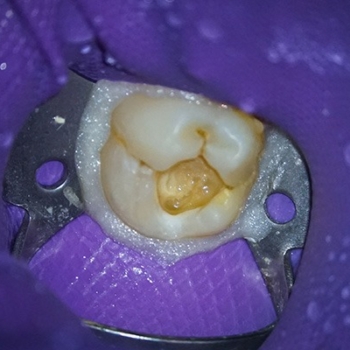

Izolarea a fost realizată folosind o digă de cauciuc, o clemă din oțel inoxidabil și digă lichidă fotopolimerizabilă plasată în jurul clemei pentru a preveni contaminarea bacteriană a zonei de tratat. Caria a fost îndepărtată circumferențial de la marginea coronară spre marginea cervicală pentru a limita intrarea bacteriilor în spațiul țesutului pulpar (9). O explorare a podelei cavității a arătat o expunere a pulpei (Figurile 3 și 4). Este întotdeauna recomandabil să explorați podeaua cavității cu un endoexplorator, deoarece o deschidere mică a camerei pulpare poate fi trecută cu vederea.

Fig. 3. & Fig. 4. Expunerea pulpară la nivelul podelei cavității, cu hemoragie minimă ușor de controlat.